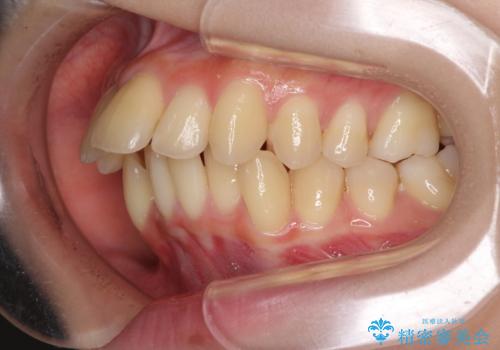

出っ歯を治したい ワイヤー装置による抜歯矯正

変則的な歯列であったため、奥歯がしっかりと咬み合うのか、前歯はしっかりと排列できるのかと不安ではありましたが、結果としてはきれいに整った歯列にて終了することができました。